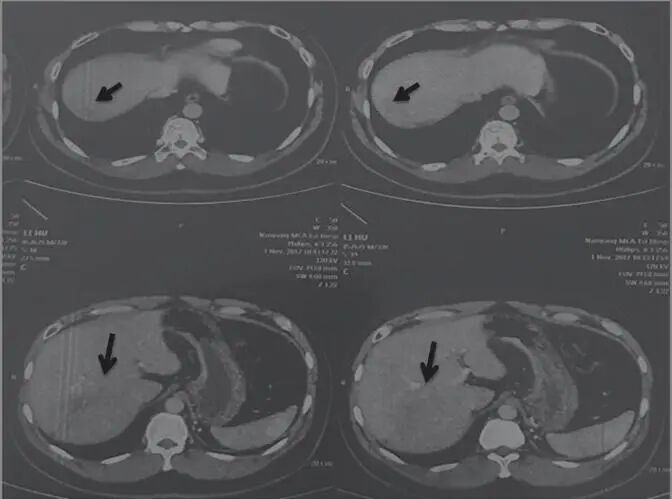

2017年11月1日,AFP 1027ng/mL查說明腫瘤并沒有消失,但是病變部位有所減?。▓D2)。

圖2 舒達(dá)少陽防治腫瘤驗案2017年11月1日CT結(jié)果